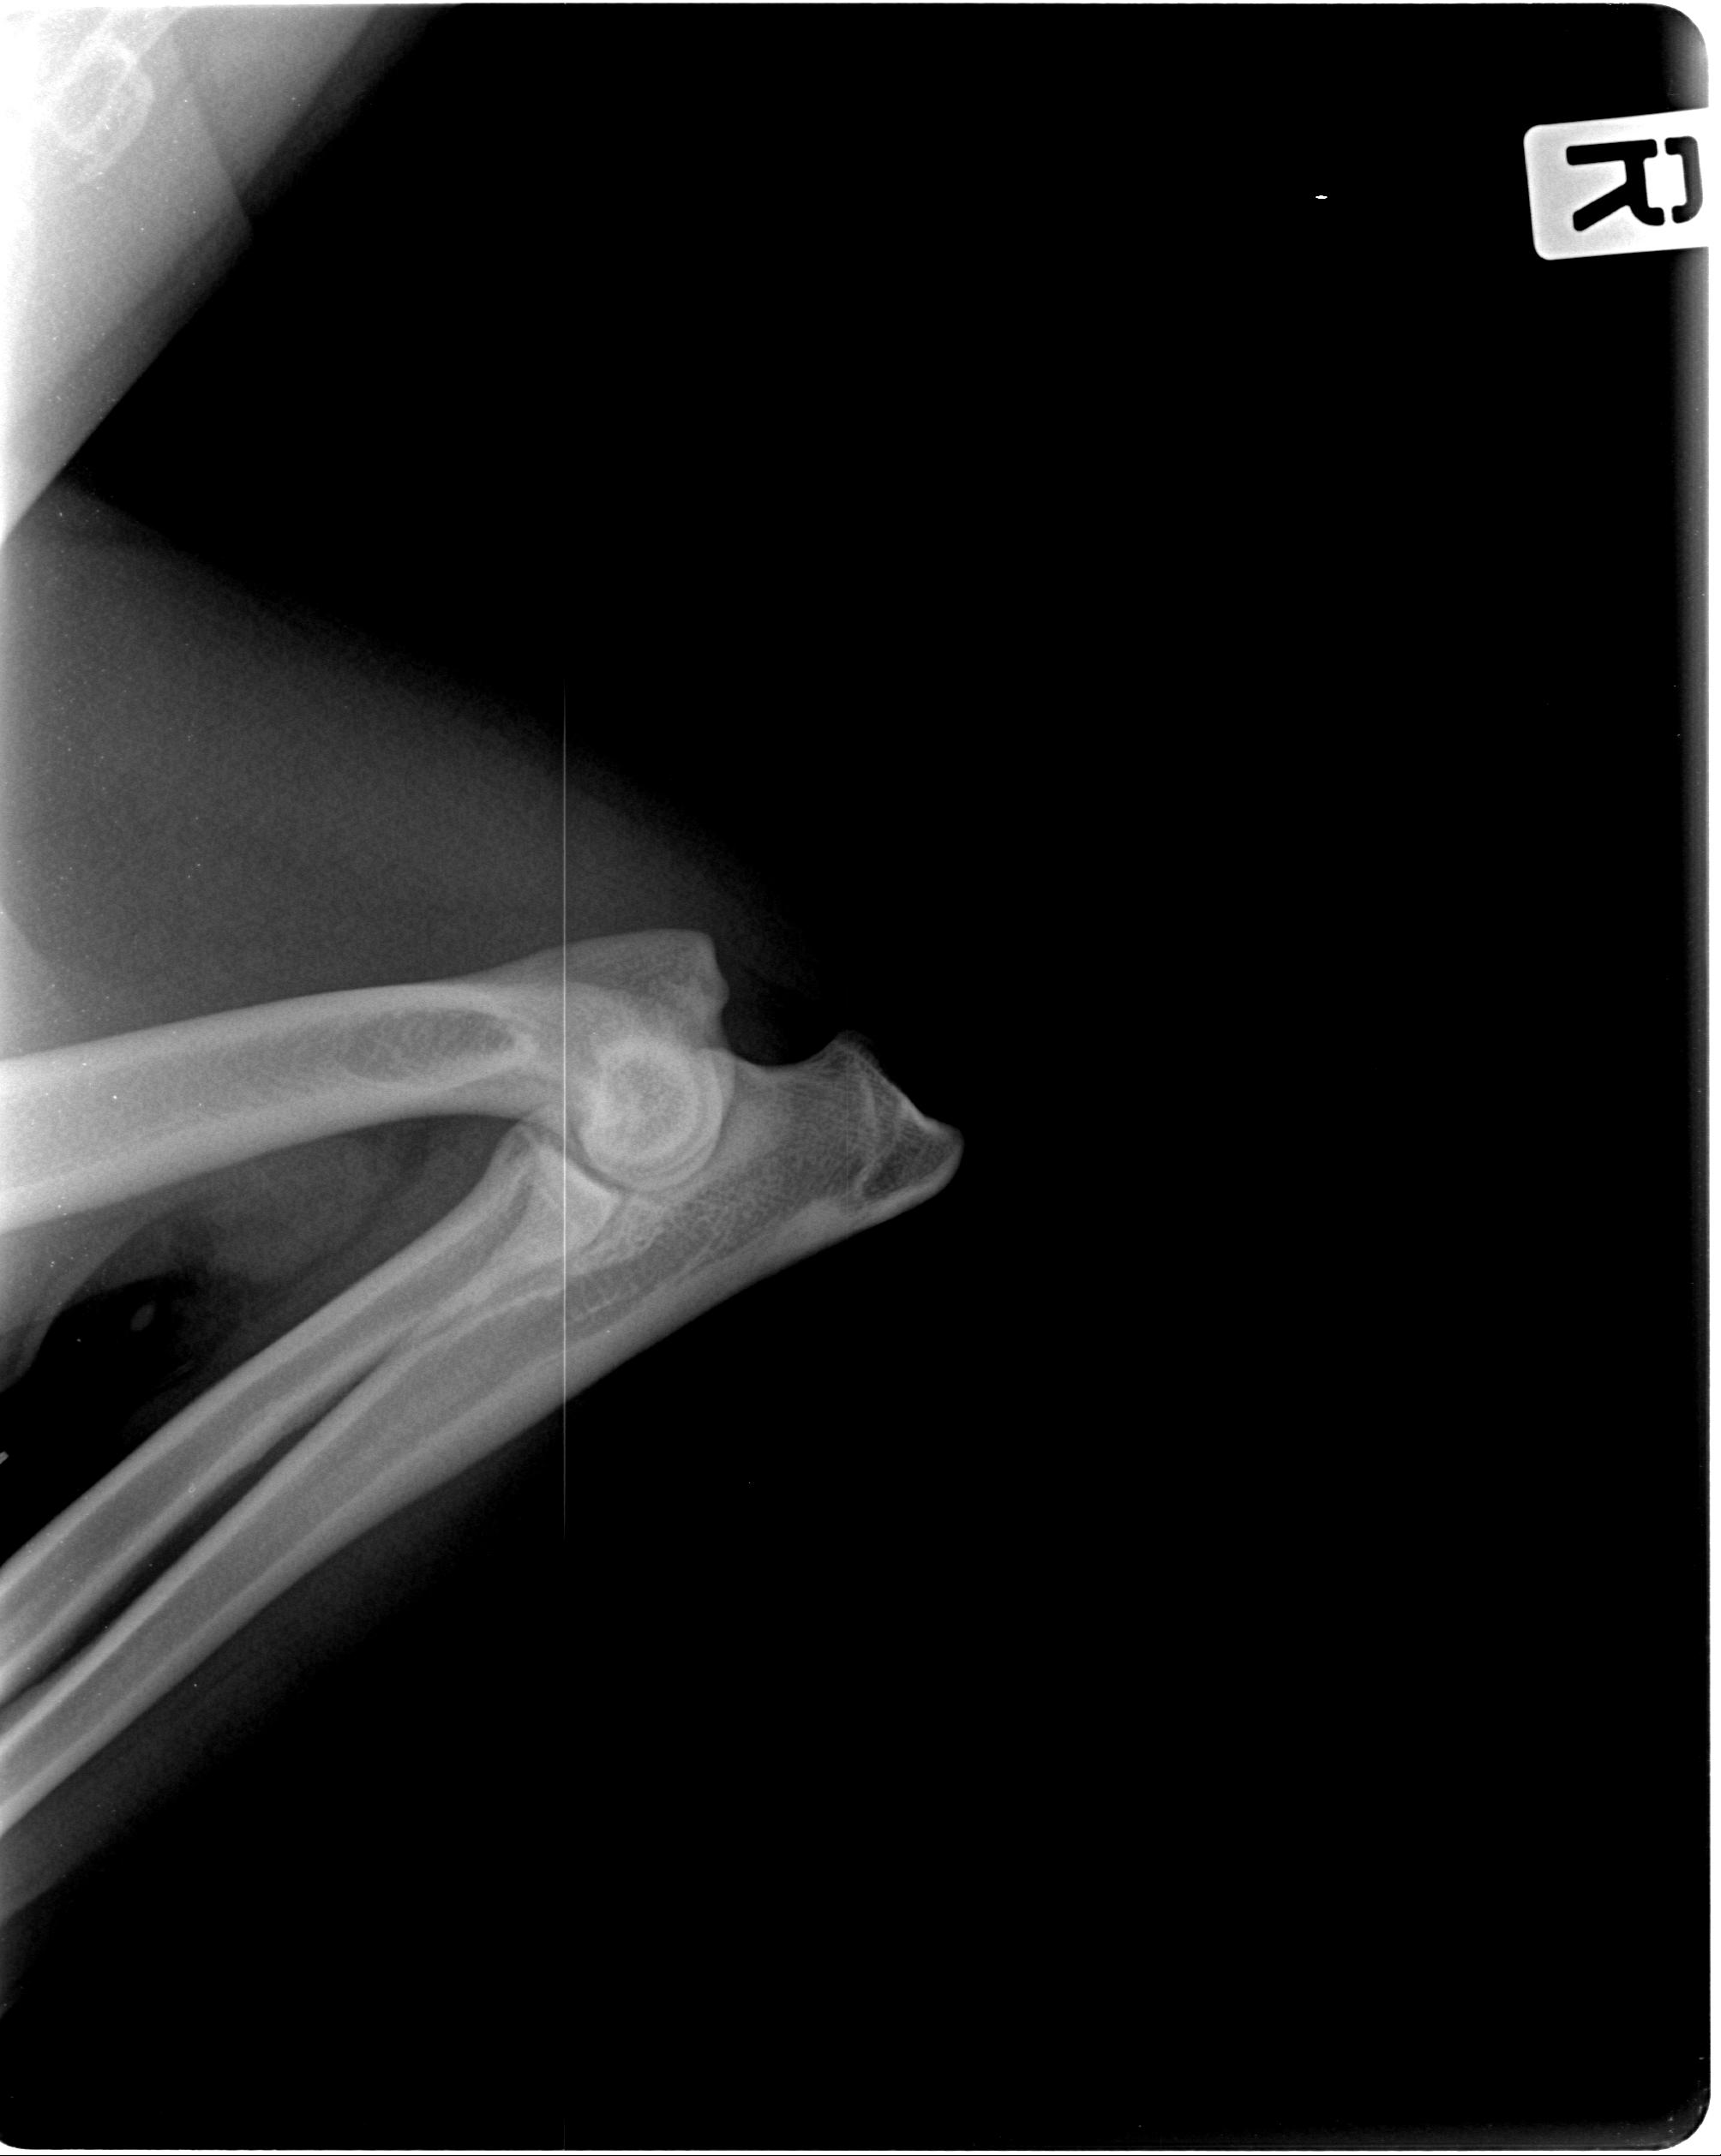

Ellenbogendysplasie (ED)

0/0

Röntgenaufnahmen

Ausgewählte Röntgenaufnahmen geben einen ergänzenden Einblick in die orthopädischen Untersuchungen dieses Zuchthundes. Die offiziellen Ergebnisse zu HD und ED finden Sie in der Übersicht oben. Weitere Nachweise stellen wir bei ernsthaftem Interesse gern zur Verfügung.